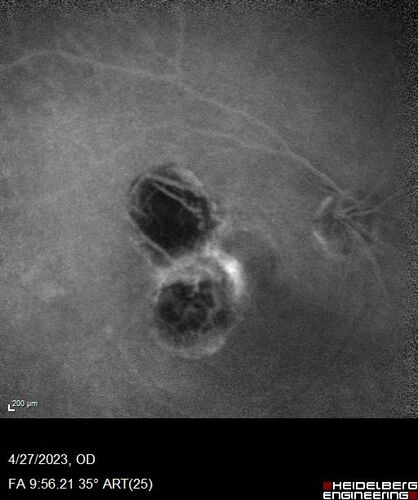

73 year old female Diagnosed with POHS in the past and treated with laser in the right eye in 1994 with vision loss.  She moved from Tampa to Largo in 2017 and started seeing Dr. Cohen.  She had her last injection in the left eye 2015 prior to moving to Largo.  She has been treated intermittently in the left eye and has been resistant to Anti-VEGF injections.  Her vision is good in the left eye. Images are from April 2023 one month following a Vabysmo injection in the left eye.

VA 20/200 OD, 20/25 OS